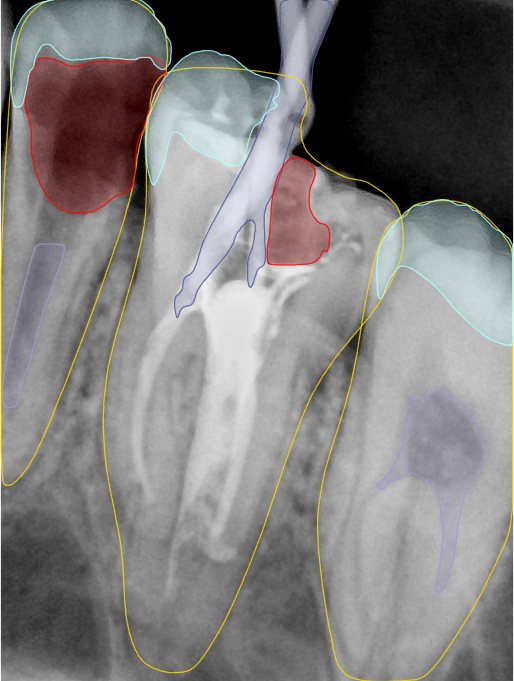

CR/DR 牙齿分割阶段记录

当前进展

- 完成了 CR/DR 牙齿相关分割训练

- 当前结果已经达到阶段预期,但仍有细节问题需要继续处理

相关测试

遇到的问题

- 训练过程中出现过 mask 下移问题

- 部分结果会出现 box 填充异常

- mask 边缘仍然有比较明显的锯齿感

参考

第二版算法问题测试

| 第一版 | 第二版 | 是否解决 | |

|---|---|---|---|

![]() | ![]() ![]() 边角识别有问题 龋齿识别不全 牙髓识别不全 | ![]() | 解决 |

![]() | ![]() 边角识别有问题 识别信息有误 自查(牙冠识别不全) | ![]() | 解决 |

![]() | ![]() ![]() 边角识别有误 大范围填充识别遗漏 | ![]() | 解决 |

![]() | ![]() 识别信息不全 | ![]() | 解决 |

![]() | ![]() ![]() 边角问题 牙胶识别不全 牙冠识别不全 | ![]() | 解决 |

![]() 换图片 | ![]() | ![]() 牙冠部分稍微白了一些就识别成小范围修补,部分判断异常 | 部分解决,修复类略敏感,牙冠部分稍微白了一些就识别成小范围修补,部分判断异常。 |

![]() | ![]() ![]() 牙冠识别不全 牙髓不全 根尖炎龋齿识别有误 | ![]() | 解决 |

![]() | ![]() | ![]() | 解决 |

![]() 换图片 | ![]() | ![]() | 解决 |

![]() | ![]() 牙冠识别有误 | ![]() | 解决 |

![]() 换图片 | ![]() ![]() 边角识别有误 | ![]() 修复类敏感 | 部分解决,图像过白,导致修复类判断异常。 |

![]() 换图片 | ![]() 牙冠识别不全 | ![]() 修复类敏感 | 部分解决,图像过白,导致修复类判断异常 |

结论:修复类出现了不鲁棒的情况,后续需要加入轮廓的扩充数据进行增强。